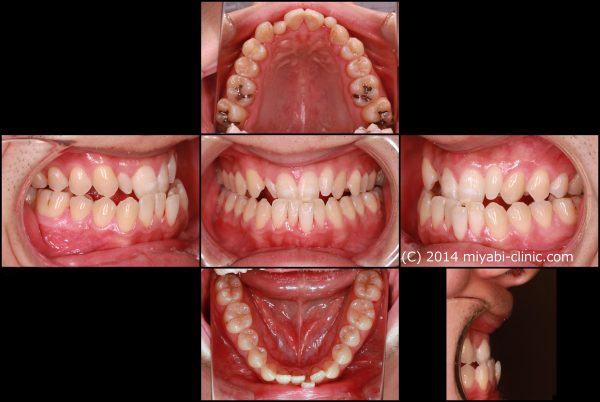

26歳 男性 「受け口を治したい」 ( 非抜歯 反対咬合 )

26歳の男性です 「受け口を治したい」との事で来院されました。

骨格的な要因を有する反対咬合です。

受け口の程度は比較的強く、難易度の高い症例です。

理想的には小児期に矯正治療により修正するべき症例です。

上の前歯に矮小歯(小さい歯)があるために、より反対の程度が大きくなっています。

お顔は上唇の張りが無く、下の唇も突出しています。

写真に写る時に笑顔で笑うのが苦手との事でした。

就職されたのを機に矯正治療を始めたいとの事でした。

ゴム掛けなどご本人の積極的なご協力もあり、

受け口は綺麗に治りました。 (*’▽’)

治療期間 20か月

2015年の11月13日にスタートして

2017年の 7月14日に終了しました

26歳 男性 叢生を伴う反対咬合 治療期間20か月 唇側矯正装置(ホワイトワイヤー) 拡大装置(ワイヤー型)を使用した非抜歯治療 参考治療費 約65万円 (精密検査から終了まで) 矯正治療に伴う副作用の歯肉退縮、知覚過敏、失活、歯根吸収などは認められませんでした。